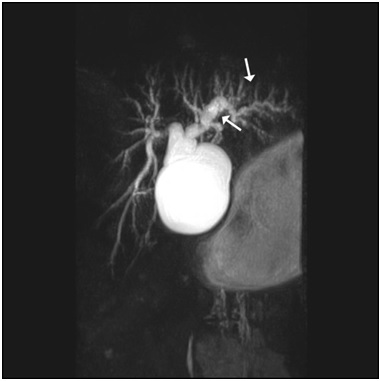

Figure 1: MRCP images obtained four months prior to biloma formation. The intrahepatic bile ducts appear wide (pruned-tree appearance). Ductal dilatation is more pronounced in the left intrahepatic bile ducts.

figure 1